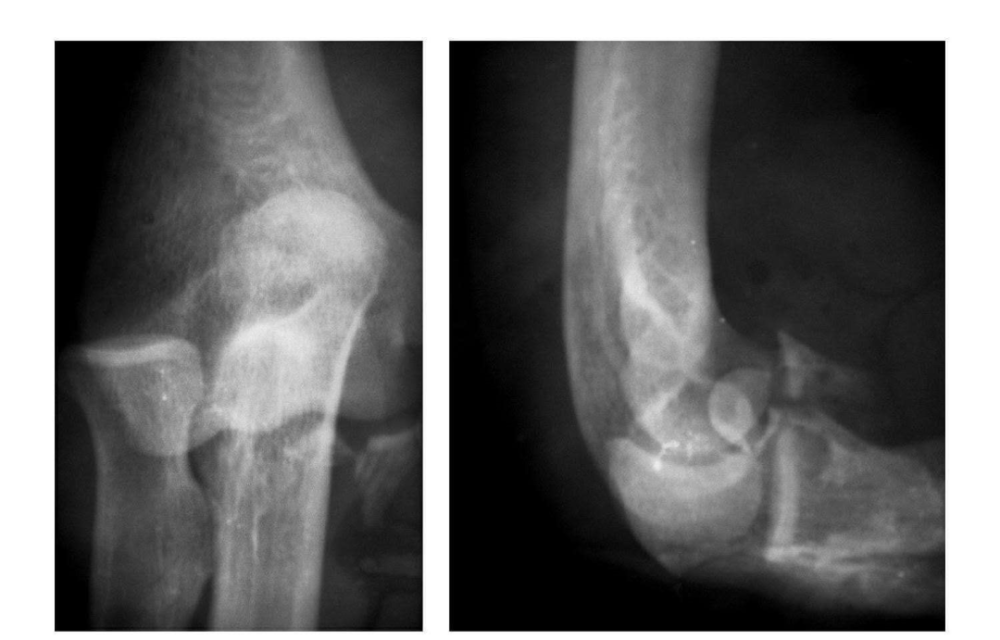

影像基础 肘关节骨折的影像学诊断及分型 移位